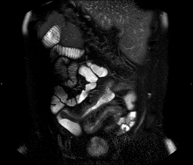

- MRI enterography (MRE)

This non-invasive diagnostic procedure uses an electromagnetic field and radio waves (from a transmitter and receiver) to acquire high-definition anatomical images of the intestines. It is a radiation-free procedure. It usually entails the use of a paramagnetic contrast (gadolinium). It is mainly indicated for the diagnosis, monitoring and control of response to treatment in patients with Crohn's disease.